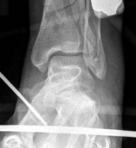

A 38-year-old woman was involved in a motor vehicle accident. She experienced immediate pain and noticed her left lower extremity was deformed. In the emergency department, x-rays showed a displaced metaphyseal fracture of the distal tibia with articular involvement (AO/OTA 43C3.3(5b) with a 4F3B fibular fracture), and posterior dislocation of the tibiotalar joint (Fig 2.2-1). The fracture was closed.

Fig 2.2-1a–b Immediate postinjury x-rays.

1. Comminuted pilon fracture (AO/OTA 43C3.3[5b]) with 4F3B fibular fracture (AP view).

2. Posterior dislocation of the tibiotalar joint (lateral view).